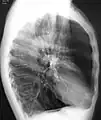

A chest X-ray is not useful to establish a diagnosis of COPD but it is of use in either excluding other conditions or including comorbidities such as pulmonary fibrosis and bronchiectasis. Characteristic signs of COPD on X-ray include hyperinflation (shown by a flattened diaphragm and an increased retrosternal air space) and lung hyperlucency.[5] A saber-sheath trachea may also be shown that is indicative of COPD.[110]

A CT scan is not routinely used except for the exclusion of bronchiectasis.[5] An analysis of arterial blood is used to determine the need for oxygen supplementation and assess for high levels of carbon dioxide in the blood; this is recommended in those with an FEV1 less than 35% predicted, those with a peripheral oxygen saturation less than 92% and those with symptoms of congestive heart failure.[111] WHO recommends that all those diagnosed with COPD be screened for alpha-1 antitrypsin deficiency.[42]